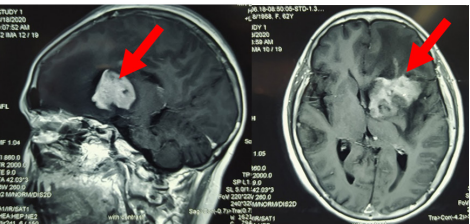

7. U não

là căn bệnh đặc trưng bởi sự hình thành mô bất thường ở cả não và tủy sống. Có rất nhiều loại khối u, do đó, các triệu chứng sẽ khác nhau tùy thuộc vào vị trí của khối u. Bên cạnh đó, kích thước và tốc độ tăng trưởng của khối u cũng sẽ quyết định các triệu chứng lâm sàng ở người bệnh.

Một số biểu hiện phổ biến nhất ở bệnh nhân u não là:

- Đau đầu hoặc nhức đầu;

- Các đợt co giật vùng đầu;

- Khó tập trung, khó nói chuyện;

- Thay đổi hành vi;

- Yếu hoặc tê liệt một bên cơ thể;

- Mất thị lực và thính lực;

- Lú lẫn và mất phương hướng;

- Hay quên, thậm chí mất trí nhớ.

Phương pháp điều trị các khối u của hệ thần kinh trung ương phụ thuộc vào các yếu tố: kích thước, vị trí khối u, triệu chứng bệnh, tình trạng sức khỏe và sở thích điều trị của người bệnh. Các phương pháp điều trị thường được áp dụng là phẫu thuật, xạ trị và hóa trị.